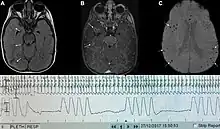

| Graph showing Biot's respiration and other pathological breathing patterns. | |